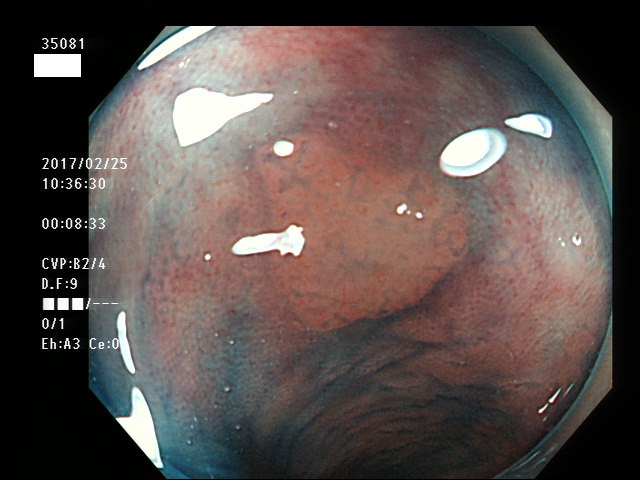

上記100名より抽出した平坦・陥凹型腺腫・SSAP(=癌化の危険が高いが見落としやすい病変)の内視鏡写真

35063 35064 35065 35066 35067 35068 35069 35071 35074 35076 35079 35081